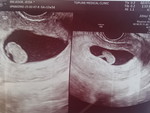

Hello mga momshies... kagabi habang nakahiga, para akong nalulunod... 13w preggy na ako... and then parang nangangalay yung hita hanggang paa ko . Any tips naman po. Salamat sa lahat